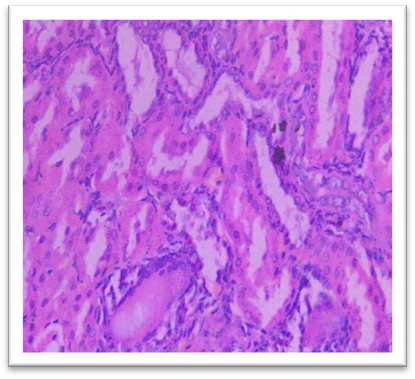

Histopathology

On day 42, rats were sacrificed for histopathological examination. Group I (Normal) and Group II (Lanthanum Carbonate only) showed normal kidney and liver architecture. Group III (Chronic Kidney Disease control) exhibited kidney damage, including crystals, congestion, haemorrhage, interstitial nephritis, and tubular dilatation. Group IV (Lanthanum Carbonate @150 mg/kg) showed moderate kidney fibrosis, mononuclear infiltration, and crystals. Group V (Lanthanum Carbonate @250 mg/kg) had mild fibrosis and sparse crystals. Group VI (Lanthanum Carbonate @500 mg/kg) showed minimal fibrosis and negligible crystals. Group VII (Lanthanum Carbonate @750 mg/kg) had minimal lesions with no crystals. Liver sections were normal in all groups. Histopathology studies revealed , The kidneys from a Chronic Kidney Disease (CKD) control rat (Group III) displayed significant macroscopic changes, including an increase in overall kidney size and the presence of multifocal, pinpoint, white granular raised lesions that were widely dispersed across the cortical surface. These observations are consistent with pathological alterations associated with CKD. Similar findings were reported by Yang et al. (2013) and Ali et al. (2015), who observed renal tissues exhibiting varying degrees of swelling and the presence of widespread white granular deposits on the cortical surfaces, consistent with the pathological features described in this study. Damment et al. (2011) observed significant changes in kidney architecture of Adenine induced Chronic Kidney Disease animals. The kidney from Group VII, treated with Lanthanum Carbonate @ 150mg/kg, 250mg/kg , 500mg/kg and 750 mg/kg body weight, demonstrated significant architectural improvement, along with a notable reduction in the number of crystalline deposits, indicating a substantial restoration of renal morphology and potential therapeutic efficacy at this dosage.

Fig. 21 Group V Kidney exhibits mild and focal interstitial fibrosis, sparse mononuclear cell infiltration, mild tubular dilatation, and 1- 2 crystals under H & E 400X.

Fig. 22 Group VI Kidney shows minimal focal fibrosis alongside mononuclear cell infiltration, crystals are nearly absent under 400X.

Fig. 23 Group VII Kidney shows very minimal or nearly absent lesions, including fibrosis and mononuclear cell infiltration, with crystals being absent under H & E 400X.